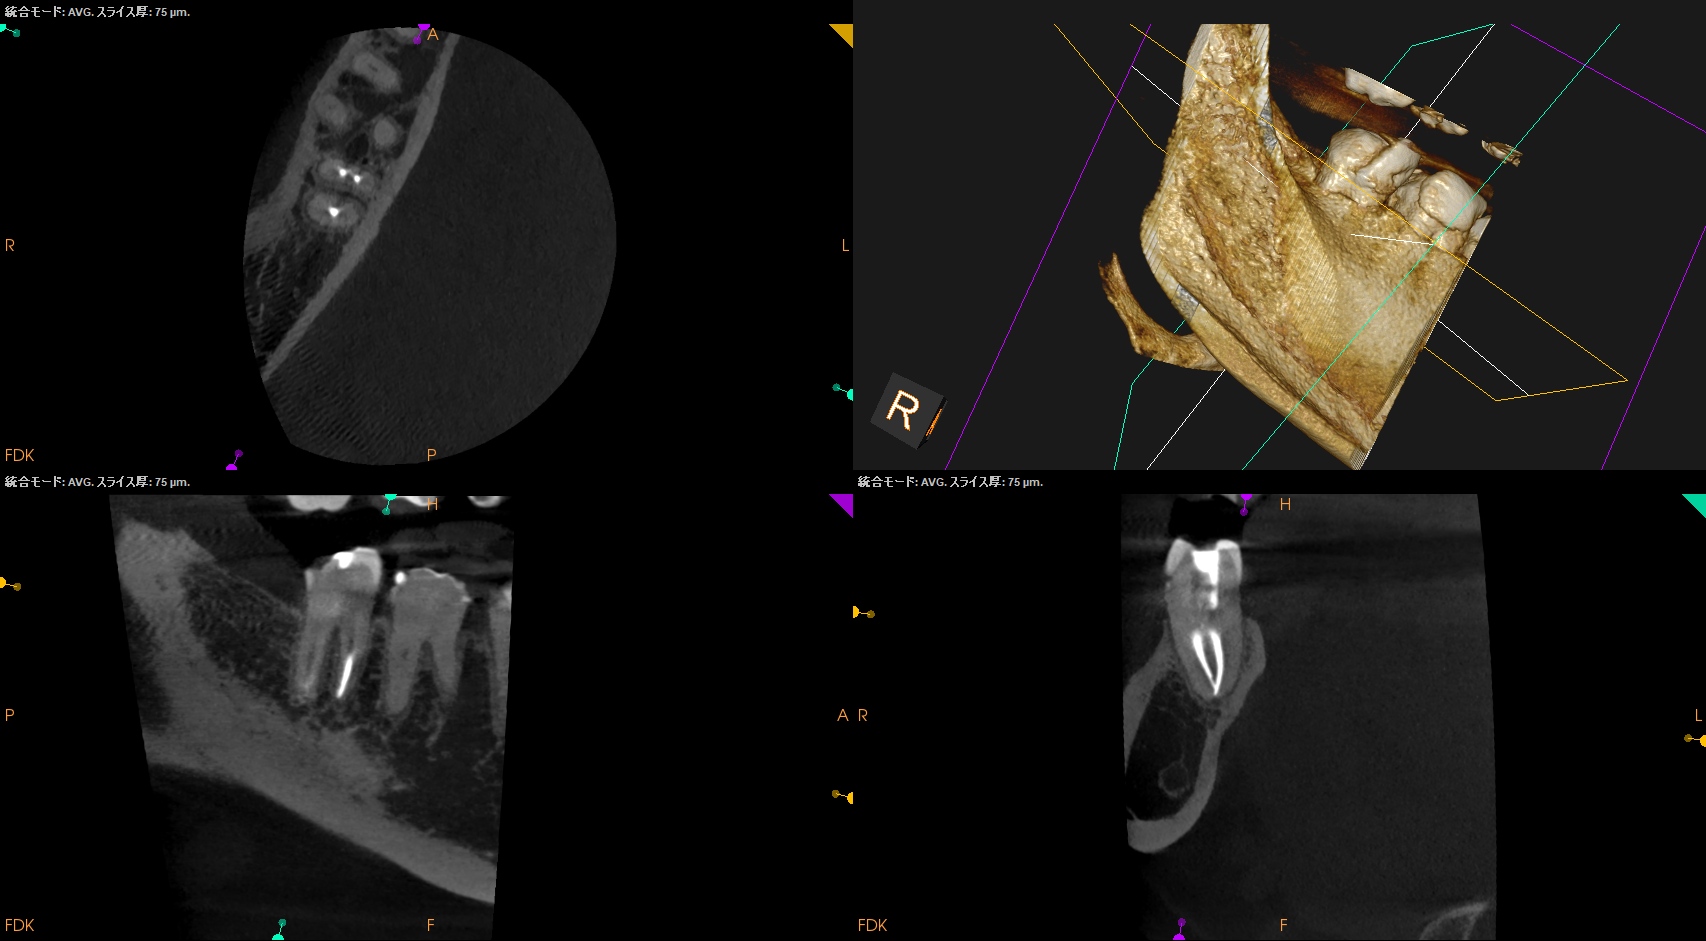

Pre-op Endo test(2026.1.26)

#31 Cold++1/15, Perc.(+), Palp.(-), BT(-), Perio Probe(WNL), Mobility(WNL)

遠心根に直接覆髄的な治療で痛みが出ている。

そして根尖部にはかなり小さいが病変的なものが見える。

#31 RCT(2026.1.26)

Inlayを除去後に根管治療が始まった。

以下のように根管形成した。

Dは#60.02で形成しても出血がペーパーポイントに見られたためにProTaper Gold F5まで形成した。